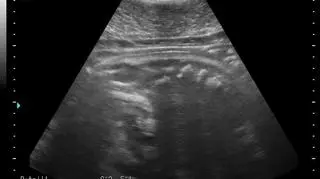

Agata, Ewa, Unda Marina i Ania spodziewają się potomstwa. Potwierdziło to pierwsze badanie USG, które przeszły foki. Nowi podopieczni pojawią się w helskim fokarium na przełomie lutego i marca.

Dobra nowinę ogłosili pracownicy Stacji Morskiej UG na jednym z portali społecznościowych, gdzie umieścili pierwsze zdjęcia maluchów.

- Po oddaniu do użytku najgłębszego basenu hodowlanego, udało nam się przeprowadzić badania USG w dogodnym dla zwierząt i opiekunów miejscu. Z radością więc informujemy, że tego roku wszystkie nasze cztery samice spodziewają się potomstwa - napisali.